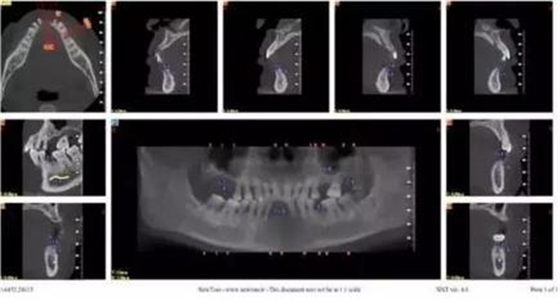

拔牙前CT截圖

手術(shù)導(dǎo)板數(shù)據(jù)發(fā)送至成都登特,通過BEGO打印機(jī)打印出導(dǎo)板,切削出臨時(shí)冠

修復(fù)后全景片